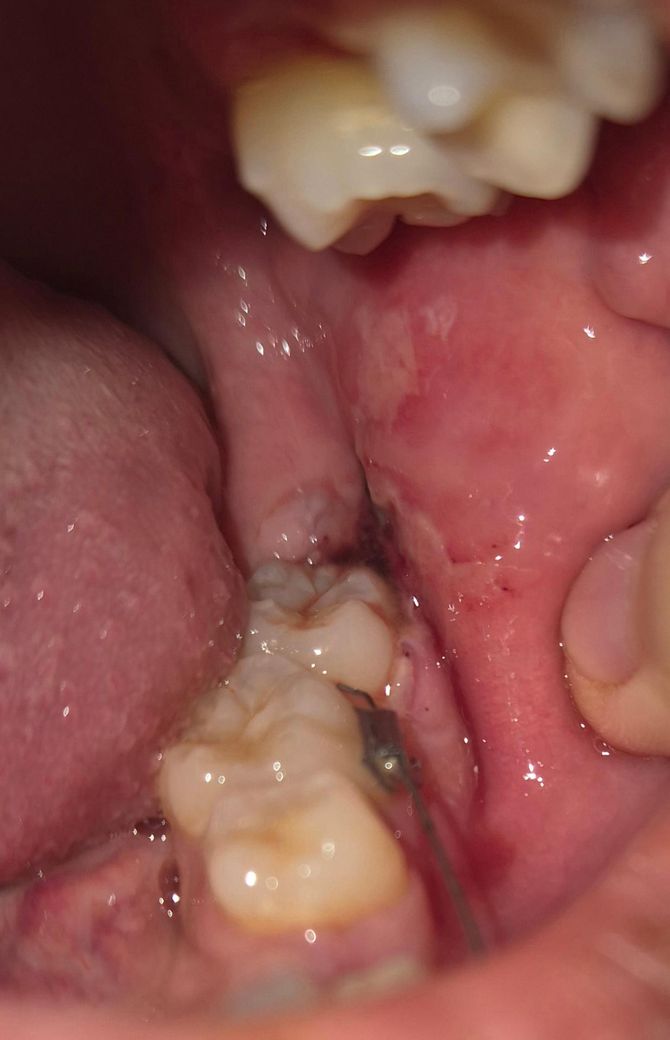

어제 거즈 4번정도 갈면서 지혈했고 1번째 사진은 오전10시쯤밥, 약먹고 난뒤입니다. 거즈문 상태로 자고 4시쯤 일어나서 밥먹고 약먹었는데 피맛이 아니라 이상한 맛 나는데 감염된 걸까요? 2,3번째사진

• 3번 째 사진